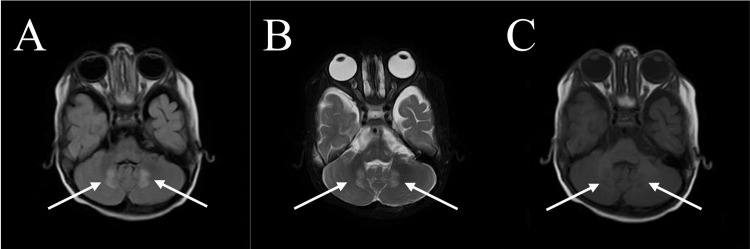

Case presentation: We present a case of a 10-year-old boy with ALD who presented with seizures, progressive weakness, visual impairment, and adrenal insufficiency. Despite symptomatic management and dietary adjustments, the disease progressed rapidly, leading to respiratory failure and eventual demise. The diagnosis was confirmed through molecular analysis and elevated VLCFA levels. Neuroimaging revealed characteristic white matter changes consistent with ALD.